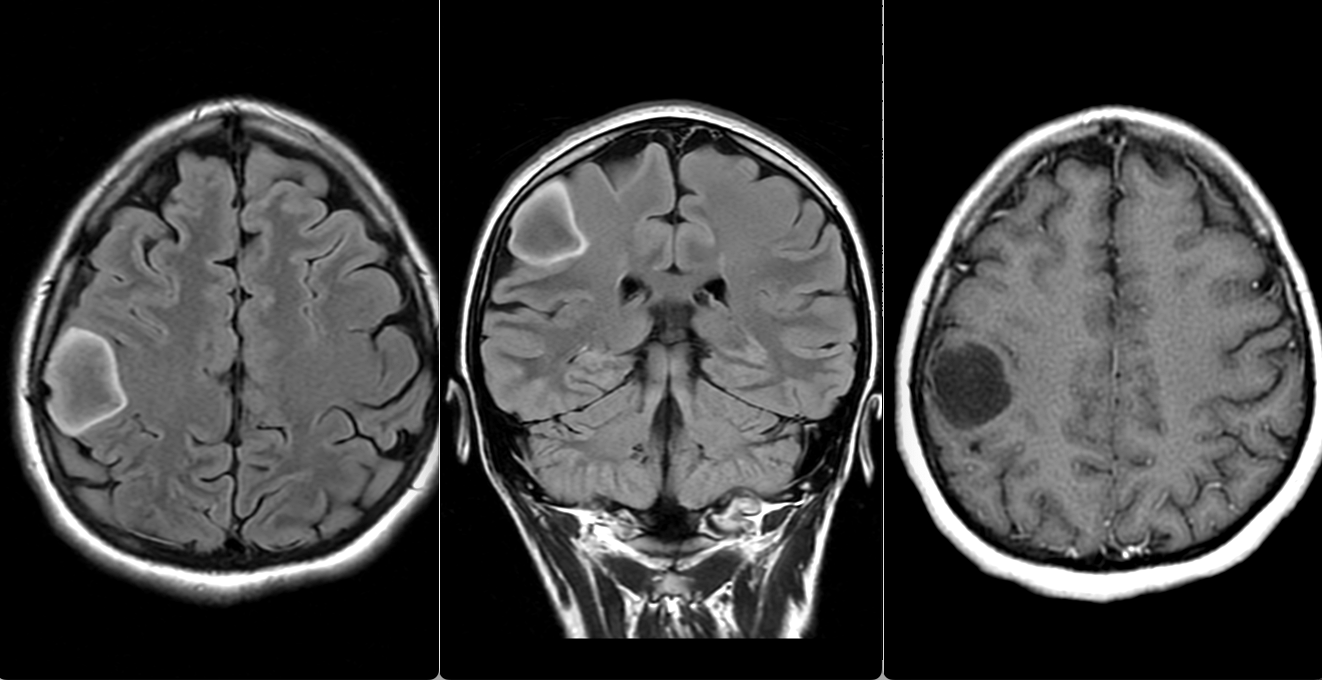

Astrocitom difuz grad II frontal drept

RMN cerebral cu contrast – metoda standard pentru caracterizarea glioamelor. Glioamele de grad mic apar ca leziuni hipointense pe T1, hiperintense pe T2, fără captare de contrast. În mod uzual se consideră că dacă un gliom de grad mic are o zonă cu priză de contrast pe RMN el este de grad III – anaplazic (grad înalt).

Gliom de grad mic frontal drept - absența prizei de contrast